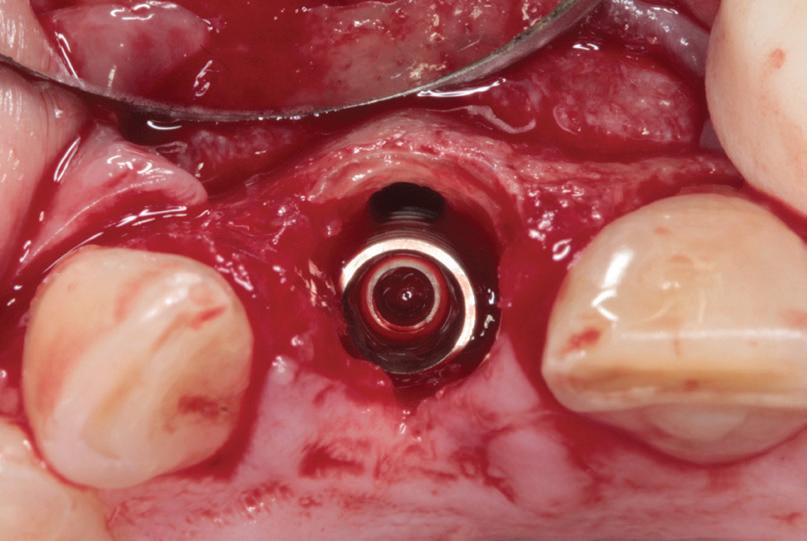

RECONSTITUIREA țesuturilor moi periimplantare. Scopul acestui raport de caz este de a demonstra procedurile chirurgicale utilizate pentru corectarea unui defect al țesuturilor moi periimplantare folosind țesutul moale interdentar în combinație cu tuberozitatea ca locație donatoare de țesut conjunctiv, utilizând o abordare prin tunelizare într-o zonă estetică.

Utilizarea platform-switch și-a dovedit eficiența în sistemele moderne de implanturi. Însă acum, zona conică inversată oferă mai mult spațiu și un suport mai bun de aderență pentru țesutul dur și moale decât formele cilindrice ale implanturilor, așa cum cum se poate vedea în imaginea următoare.

Suprafața microstructurată din zona conică inversată sprijină atașarea osului și a țesutului conjunctiv. Atunci când marginea acesteia este poziționată subcrestal, este recomandată utilizarea unui material de augmentare (xenogrefă sau os autolog) care poate preveni dezvoltarea țesutului moale în zona conică inversată și poate oferi suport pentru o mai bună osteointegrare.

Datorită designului șurubului de acoperire, care are un diametru mic și formă concavă, nu se irită țesuturile periimplantare în momentul în care se intervine în vederea montării formatorului gingival. Osul nou format pe șurubul de acoperire anodizat poate fi îndepărtat cu ușurință cu ajutorul unei chiurete.